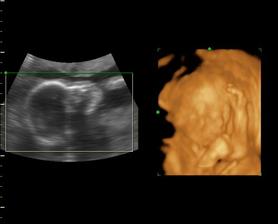

Naša Emilly

Zaciname 39tt, termin mame 23.10.09, uvidime, kedy sa malej bude chciet ist na svet a vidiet svojich rodicov. Sice sme mali neplanovane tehotenstvo, ale o to viac nas to potesilo a na malu sa nesmierne obaja tesime..je to u nas prve vnucatko, tak to bude lasky a lasky, ale tej dame aj druhemu aj tretiemu babu, uvidime, kolko nam ich zivot da. I ked mamina este studuje, urcite to zvladneme..